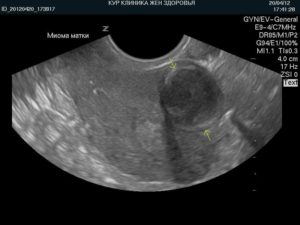

Миома матки небольших размеров чаще всего протекает без симптомов и выявляется врачом при осмотре. Бывает, что миому удается обнаружить спустя пару лет с момента формирования узла. Диагноз ставится исходя из исследований: МРТ, УЗИ, КТ.

Трансвагинальное УЗИ с использованием датчика позволяет выявить образование на начальной стадии, определить размер опухоли и её местонахождение. В дополнение к УЗИ назначается анализ кровообращения, исследование строения ткани, содержание атипичных клеток. Женщина сдает кровь на определение анемии и наличие инфекций.

Классификация

Размеры миоматозных узлов зависят от концентрации гормона эстрогена в крови. При повышении их уровня опухоль начинает расти. Акушеры-гинекологи сопоставляют размеры миоматозных узлов с неделями беременности. Однако это метод классификации миом применяют все реже. Для определения вида опухоли проводят ультразвуковое исследование.

Для определения вида опухоли проводят ультразвуковое исследование.

Оно позволяет точно определить размеры образования, вплоть до нескольких миллиметров. В этом случае классификация миом будет следующей:

Однако диагностика миомы матки малых размеров не вызывает сложностей. Гинекологический осмотр и ультразвуковое исследование помогают обнаружить малую опухоль.

На начальной стадии, когда миома матки имеет маленький размер, болезнь себя не проявляет. Характерная клиническая картина прослеживается по мере роста образования, у женщины возникают кровотечения, не имеющие связи с менструальными, боль внизу живота. Размеры матки сравнивают с габаритами плода в период беременности, подобное заключение можно получить после прохождения УЗИ.

Опасность, новообразование небольшого размера не представляет. Беспокоящие симптомы – отсутствуют, оно может быть обнаружено внимательным гинекологом в ходе планового осмотра или при проведении УЗИ.